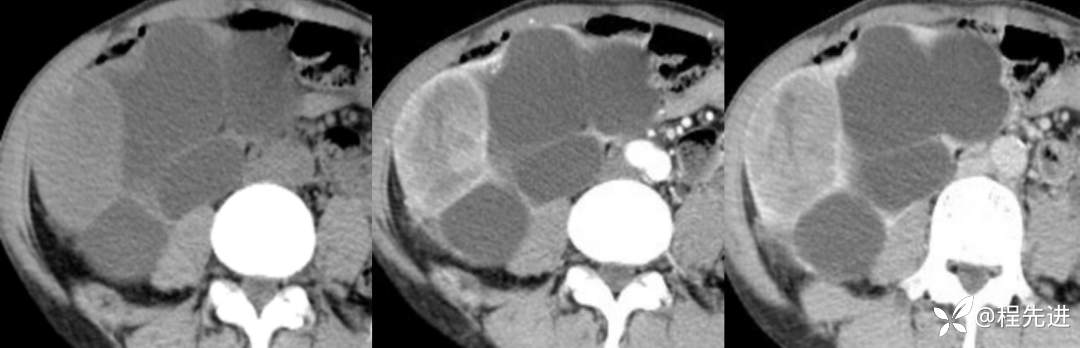

来张特定(左平扫,中动脉期,右静脉期)